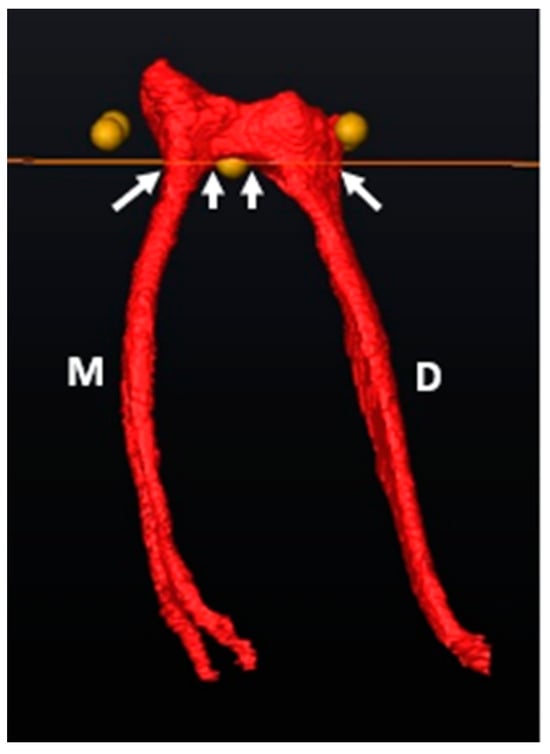

3.1. Mandibular First Molars: Two Rooted

4.1. Mandibular Molars